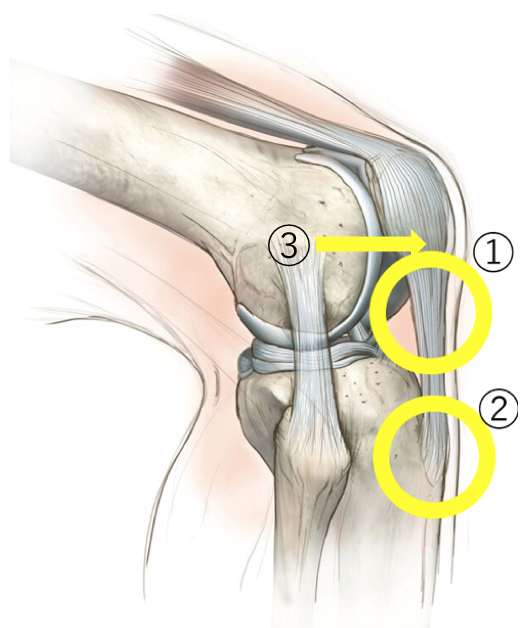

上図の①②③膝蓋腱症

①膝蓋腱実質部

②脛骨粗面

③膝蓋骨下極